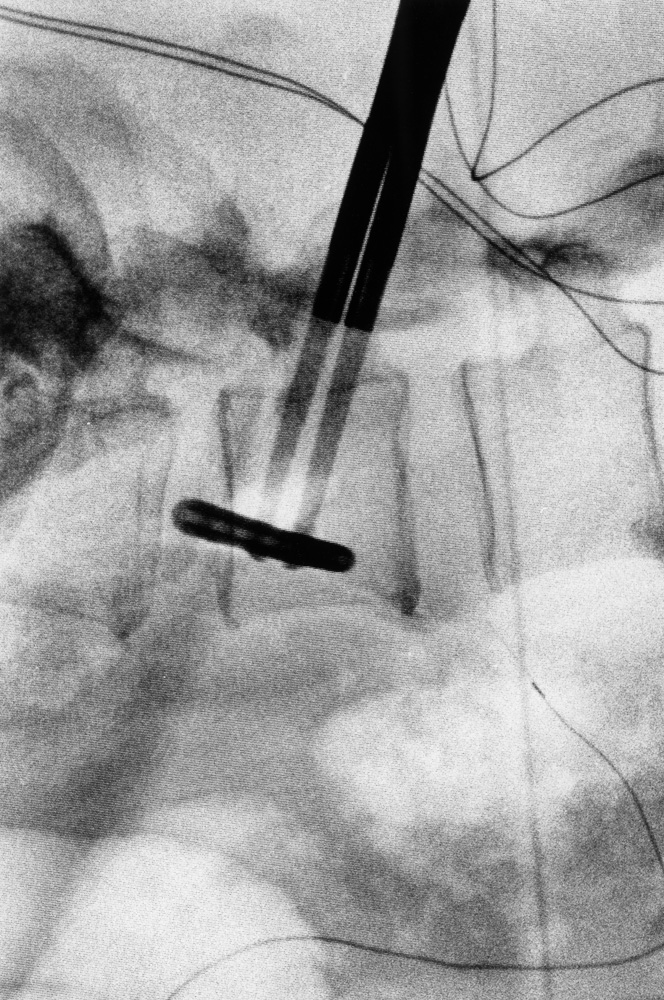

Da metà giugno a fine novembre 2021, Renato D’Agostin e la sua macchina fotografica hanno avuto accesso esclusivo alla clinica: dal centro di riabilitazione alle sale operatorie, dai reparti di degenza all’area amministrativa, dal laboratorio di analisi agli ambulatori.

Il risultato di questo viaggio immersivo nel mondo e negli spazi della struttura sono oggi 20 scatti unici e irripetibili, raccolti in questo catalogo e nella mostra “La Cura.

La clinica Rizzola nelle fotografie di Renato D’Agostin” ospitata presso Spazio Mostre Italvanto Battistella, a San Donà di Piave, dal 7 al 17 gennaio 2022 Gli scatti trovano oggi esposizione permanente all’interno della Casa di Cura Sileno e Anna Rizzola.